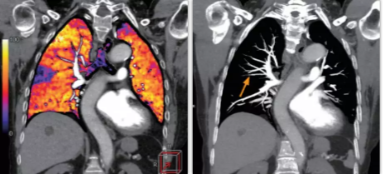

相比傳統(tǒng)成像方式,肺部柔性減影技術(shù)通過人工智能,對平掃數(shù)據(jù)和CT肺動脈血管掃描數(shù)據(jù)進行智能比對,解碼并識別各個器官(肺、氣管、肺動脈、肺靜脈、主動脈等)的空間位置,并在三維空間中進行體素級的柔性配準(zhǔn),從而極大提升了不同序列數(shù)據(jù)的空間位置的一致性。通過肺部柔性減影技術(shù)可得到肺強化碘圖,可以顯示出傳統(tǒng)CTPA圖像看不到的小栓塞病變,提高了栓塞檢出率,其結(jié)果甚至可與SPECT吻合。

肺智能柔性減影成像功能發(fā)現(xiàn)亞段肺栓塞